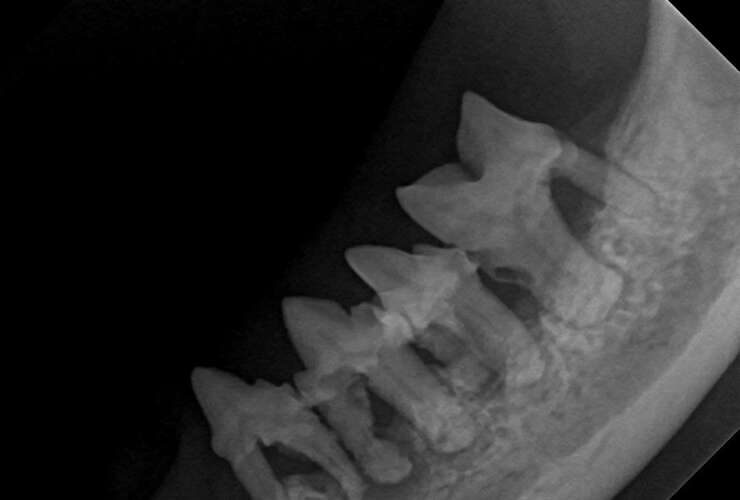

Pet Dental Care in Clemson, SC Did you know? Dental disease is the most common disease in dogs and cats. Not only does dental disease cause bad breath in dogs and cats, but it can actually lead to severe pain and serious systemic health issues! At Pinnacle Veterinary Group we focus on prevention of dental disease starting early in your…